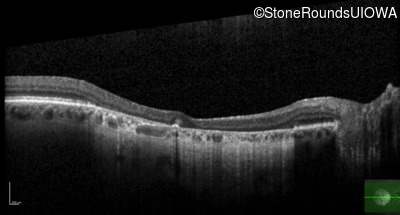

Optical Coherence Tomography - Right - 20/63 -2

Exemplar / OCT Stack

OCT Stack